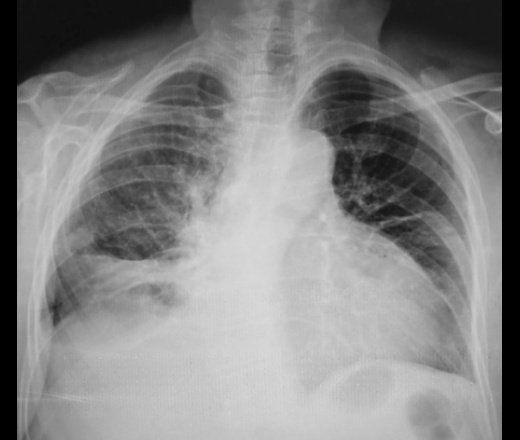

что плевральный выпот в междолевых щелях обусловлен застойной сердечной недостаточность. С какой целью была выполнена рентгенография ОГК? Возраст пациентки?

Смущает то что правый купол диафрагмы приподнят. И вопрос Даннный момент может быть из за кифосколиоза?

Полагаю,дело не только в застое.Справа может ещё что-то.Нужна клиника.

При базальном выпоте может быть до литра жидкости, а синус оставаться свободным.

Пациентка весьма преклонного возраста, за 65 лет.

Предполагали консультанты и лечащий врач перикардит.